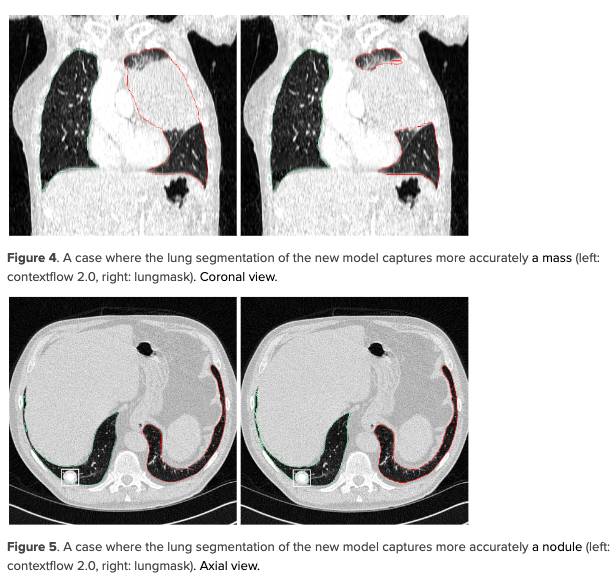

contextflow, health insurance partner IKK Südwest

Early detection is essential for successful treatment of thoracic diseases. “We offer AI software that provides additional information for identifying and interpreting lung-specific image patterns in CT scans,” says Markus Holzer, CEO and co-founder of contextflow. The ultimate goal of the software is to detect lung cancer as early as possible in order to save healthcare system resources and protect patients from unnecessary interventions. “The image analysis AI enables radiologists to assess relevant image patterns of lung cancer and respiratory diseases faster and better,” says Dr. Florian Brandt, Health Innovation Manager at IKK Südwest.